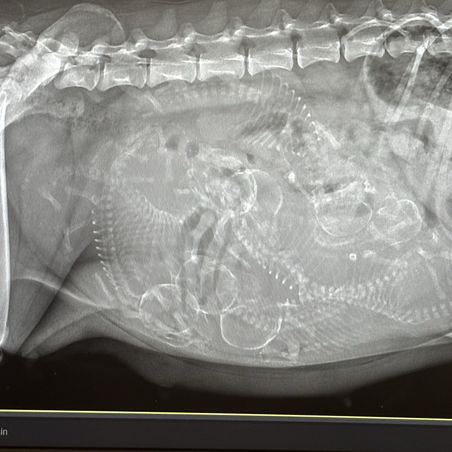

Due any day now 😍😍

Hudson and Lilly's litter